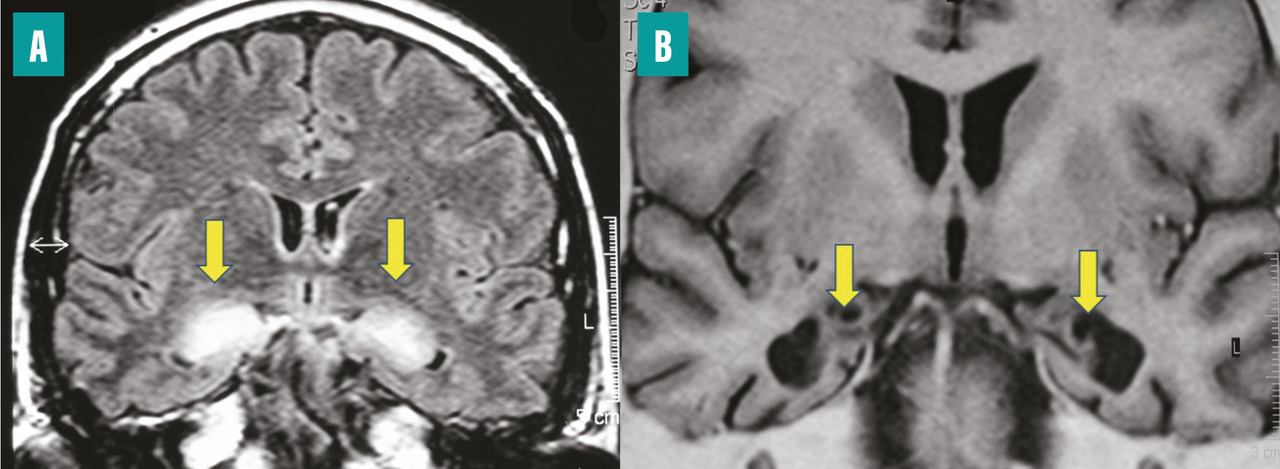

Très récemment ont été décrites des encéphalites toxiques dues à des opioïdes3 ou à des drogues telles que la MDMA (ecstasy), qui lèsent électivement le circuit de Papez (fig. 3 ).

Très récemment ont été décrites des encéphalites toxiques dues à des opioïdes3 ou à des drogues telles que la MDMA (ecstasy), qui lèsent électivement le circuit de Papez (